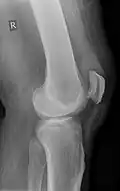

Quadriceps tendon rupture in plain X-ray

-